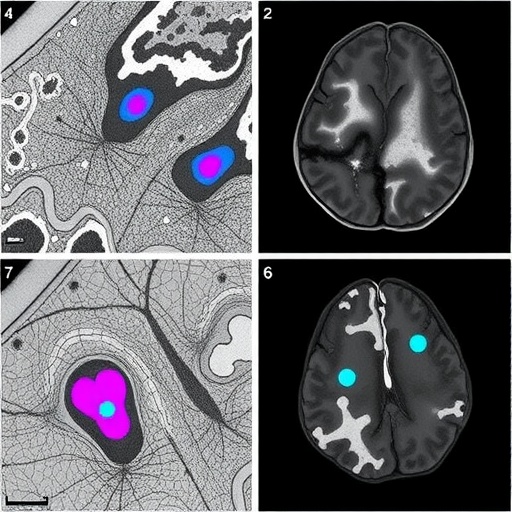

The methodology implemented by Barber-Janer and colleagues integrates high-resolution histological imaging with deep learning architectures tailored to parse complex morphological patterns. The CNN was optimized to detect alpha-synuclein aggregates, a defining pathological proteinopathy in Parkinson’s disease. This protein misfolding and aggregation cascade is a critical feature underpinning synucleinopathies, making its accurate identification essential for both diagnostic and therapeutic research.

One of the most remarkable achievements of this work is the ability to perform brain-wide mapping of pathological burden. By automating this process, the researchers could quantify and visualize spatial distribution patterns of alpha-synuclein deposits throughout different brain regions in three dimensions. Such comprehensive mapping facilitates deeper insights into disease progression, neuroanatomic vulnerability, and potential pathways for therapeutic intervention.

Beyond detection, the CNN’s analytical capacity extends to distinguishing between diverse morphological phenotypes of alpha-synuclein aggregates, ranging from small punctate inclusions to larger, more complex Lewy body-like formations. This capability introduces a new level of granularity to neuropathological studies, allowing researchers to investigate correlations between aggregate morphology and disease severity or stage.